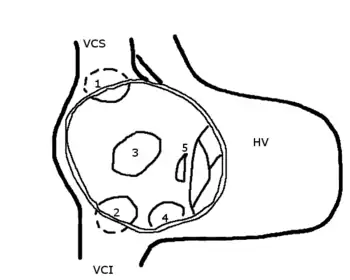

HV: right ventricle; VCS: superior vena cava; VCI: inferior vena cava

1: upper sinus venosus defect; 2: lower sinus venosus defect; 3: secundum defect; 4: defect involving coronary sinus; 5; primum defect.

The six types of atrial septal defects are differentiated from each other by whether they involve other structures of the heart and how they are formed during the developmental process during early fetal development.